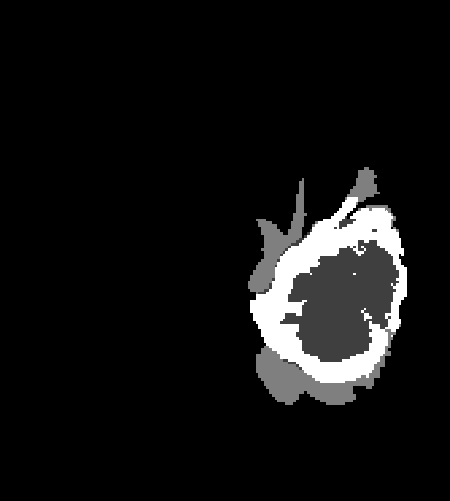

The proposed model outperforms some of the ensemble approaches which is shown in Table 4. Fig. 2 shows the successful segmentation of the tumor. The false positive segmentation voxels are removed in the post-processing. The network fails to segment the tumor for some HGG images and many LGG images. One such segmentation failure is shown in Fig. 3. The failure of the network is observed for: 1) small size of the entire tumor, 2) small size of necrosis, and 3) absence/small size of enhancing tumor. Fig. 4 depicts the box plot of the evaluation metrics, where the red marked cases shows the segmentation failure.

Refer to caption

(a)

(b)

(c)

(d)

Figure 3: Incorrect segmentation results of the network (a) FLAIR slice (b) Ground truth (c) Segmentation without post-processing (d) Segmentation after post-processing.